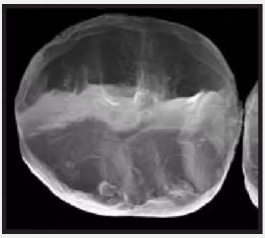

復(fù)合樹脂在即刻充填后,觀察其在電子顯微鏡下的掃描圖像,本次研究選擇了9種具有代表性的復(fù)合樹脂材料。

1.png

Clearfil Majesty Kuraray America 可樂麗